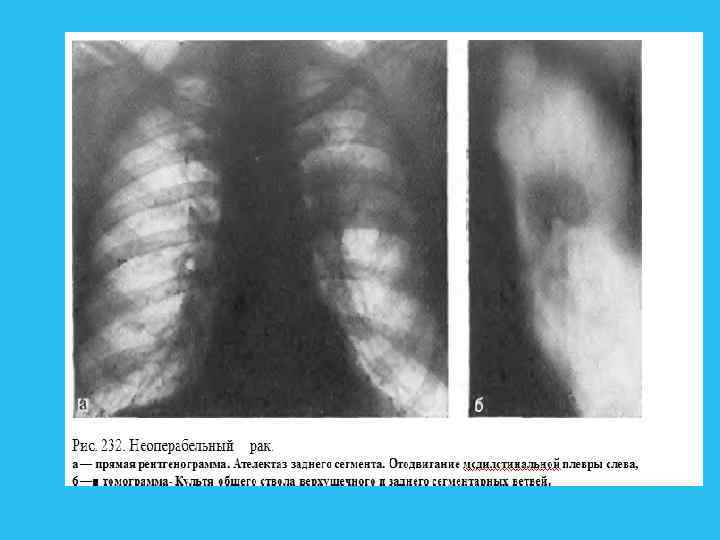

Этой ошибочной трактовке изменений помогает отсутствие видимого опухолевого узла и изображения бронхиальных разветвлепий (рис. 248).